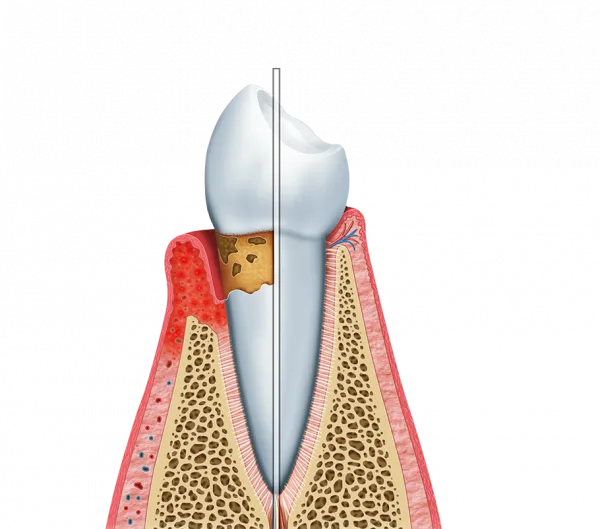

A Periodontia é a especialidade que se concentra na saúde das gengivas e dos tecidos de suporte, sendo vital para manter a dentição fixa e protegida contra infecções.

Controle de Inflamações: Tratamento eficaz para gengivite e periodontite;

Saúde Gengival: Interrupção de sangramentos e redução da sensibilidade;

Proteção Óssea: Preservação do osso que sustenta as raízes dentais.

Isso inclui procedimentos como a raspagem e alisamento radicular, o controle rigoroso da placa bacteriana e instruções personalizadas de higiene bucal para o dia a dia.